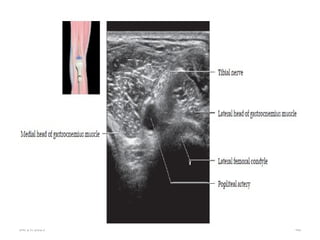

 Ultrasound

 Use high-frequency transducers to assess nerves.

 Short axis: A typical “honeycomb” appearance with hypoechoic

fascicles and surrounding echogenic perineurium

 Long axis: Parallel hypoechoic tracts of uniform caliber.

 Distortion of this uniform appearance suggests pathology

04/29/2025 42

• Trace medium-sized nerves by following their course as they

branch from their parent.

• Small (1-2 mm) nerves are difficult to identify and location

may only be inferred by adjacent vessels.